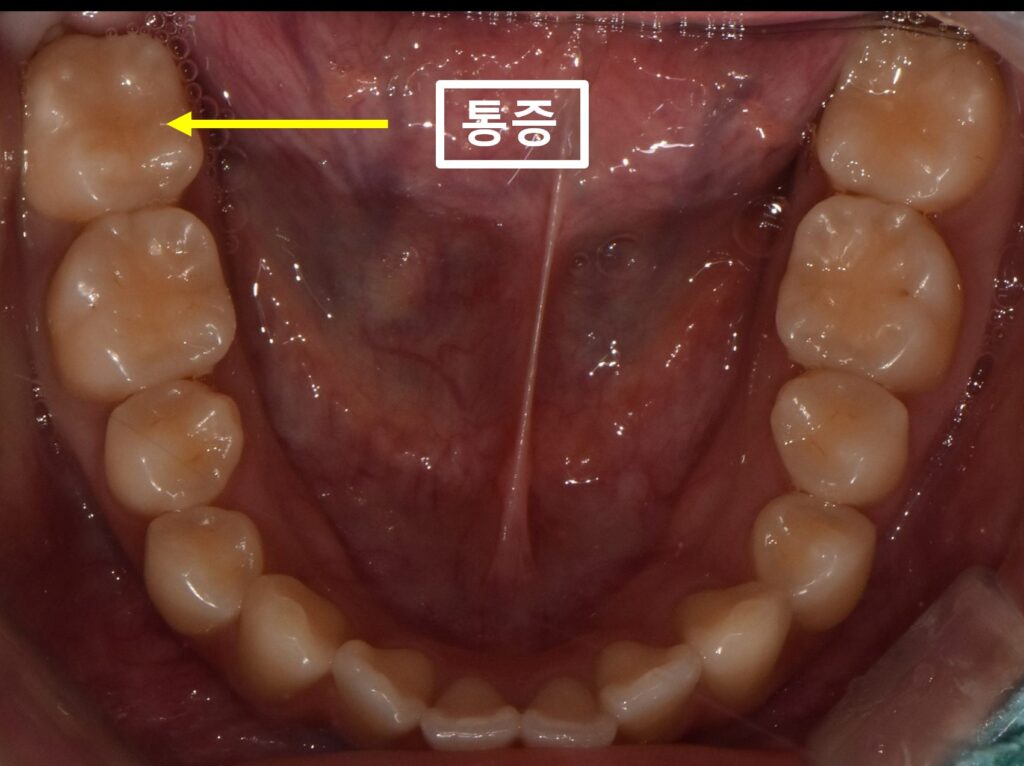

먼저 입안 사진입니다.

노랑색화살표가 가리키는 치아가

계속 불편하고, 주변 잇몸도 양치할때 아파서

집근처 치과에 갔는데

금으로 씌워진 치아는 이상이 없다고

들었다고 하셨습니다.

저도

치아 두드려보거나

찬물 혹은 따뜻한 물에 통증이 있는지,

잇몸 아래로 염증으로 인한 주머니가 있는지

면밀한 검사를 했지만

치아 자체에는 큰 이상이 없었습니다.